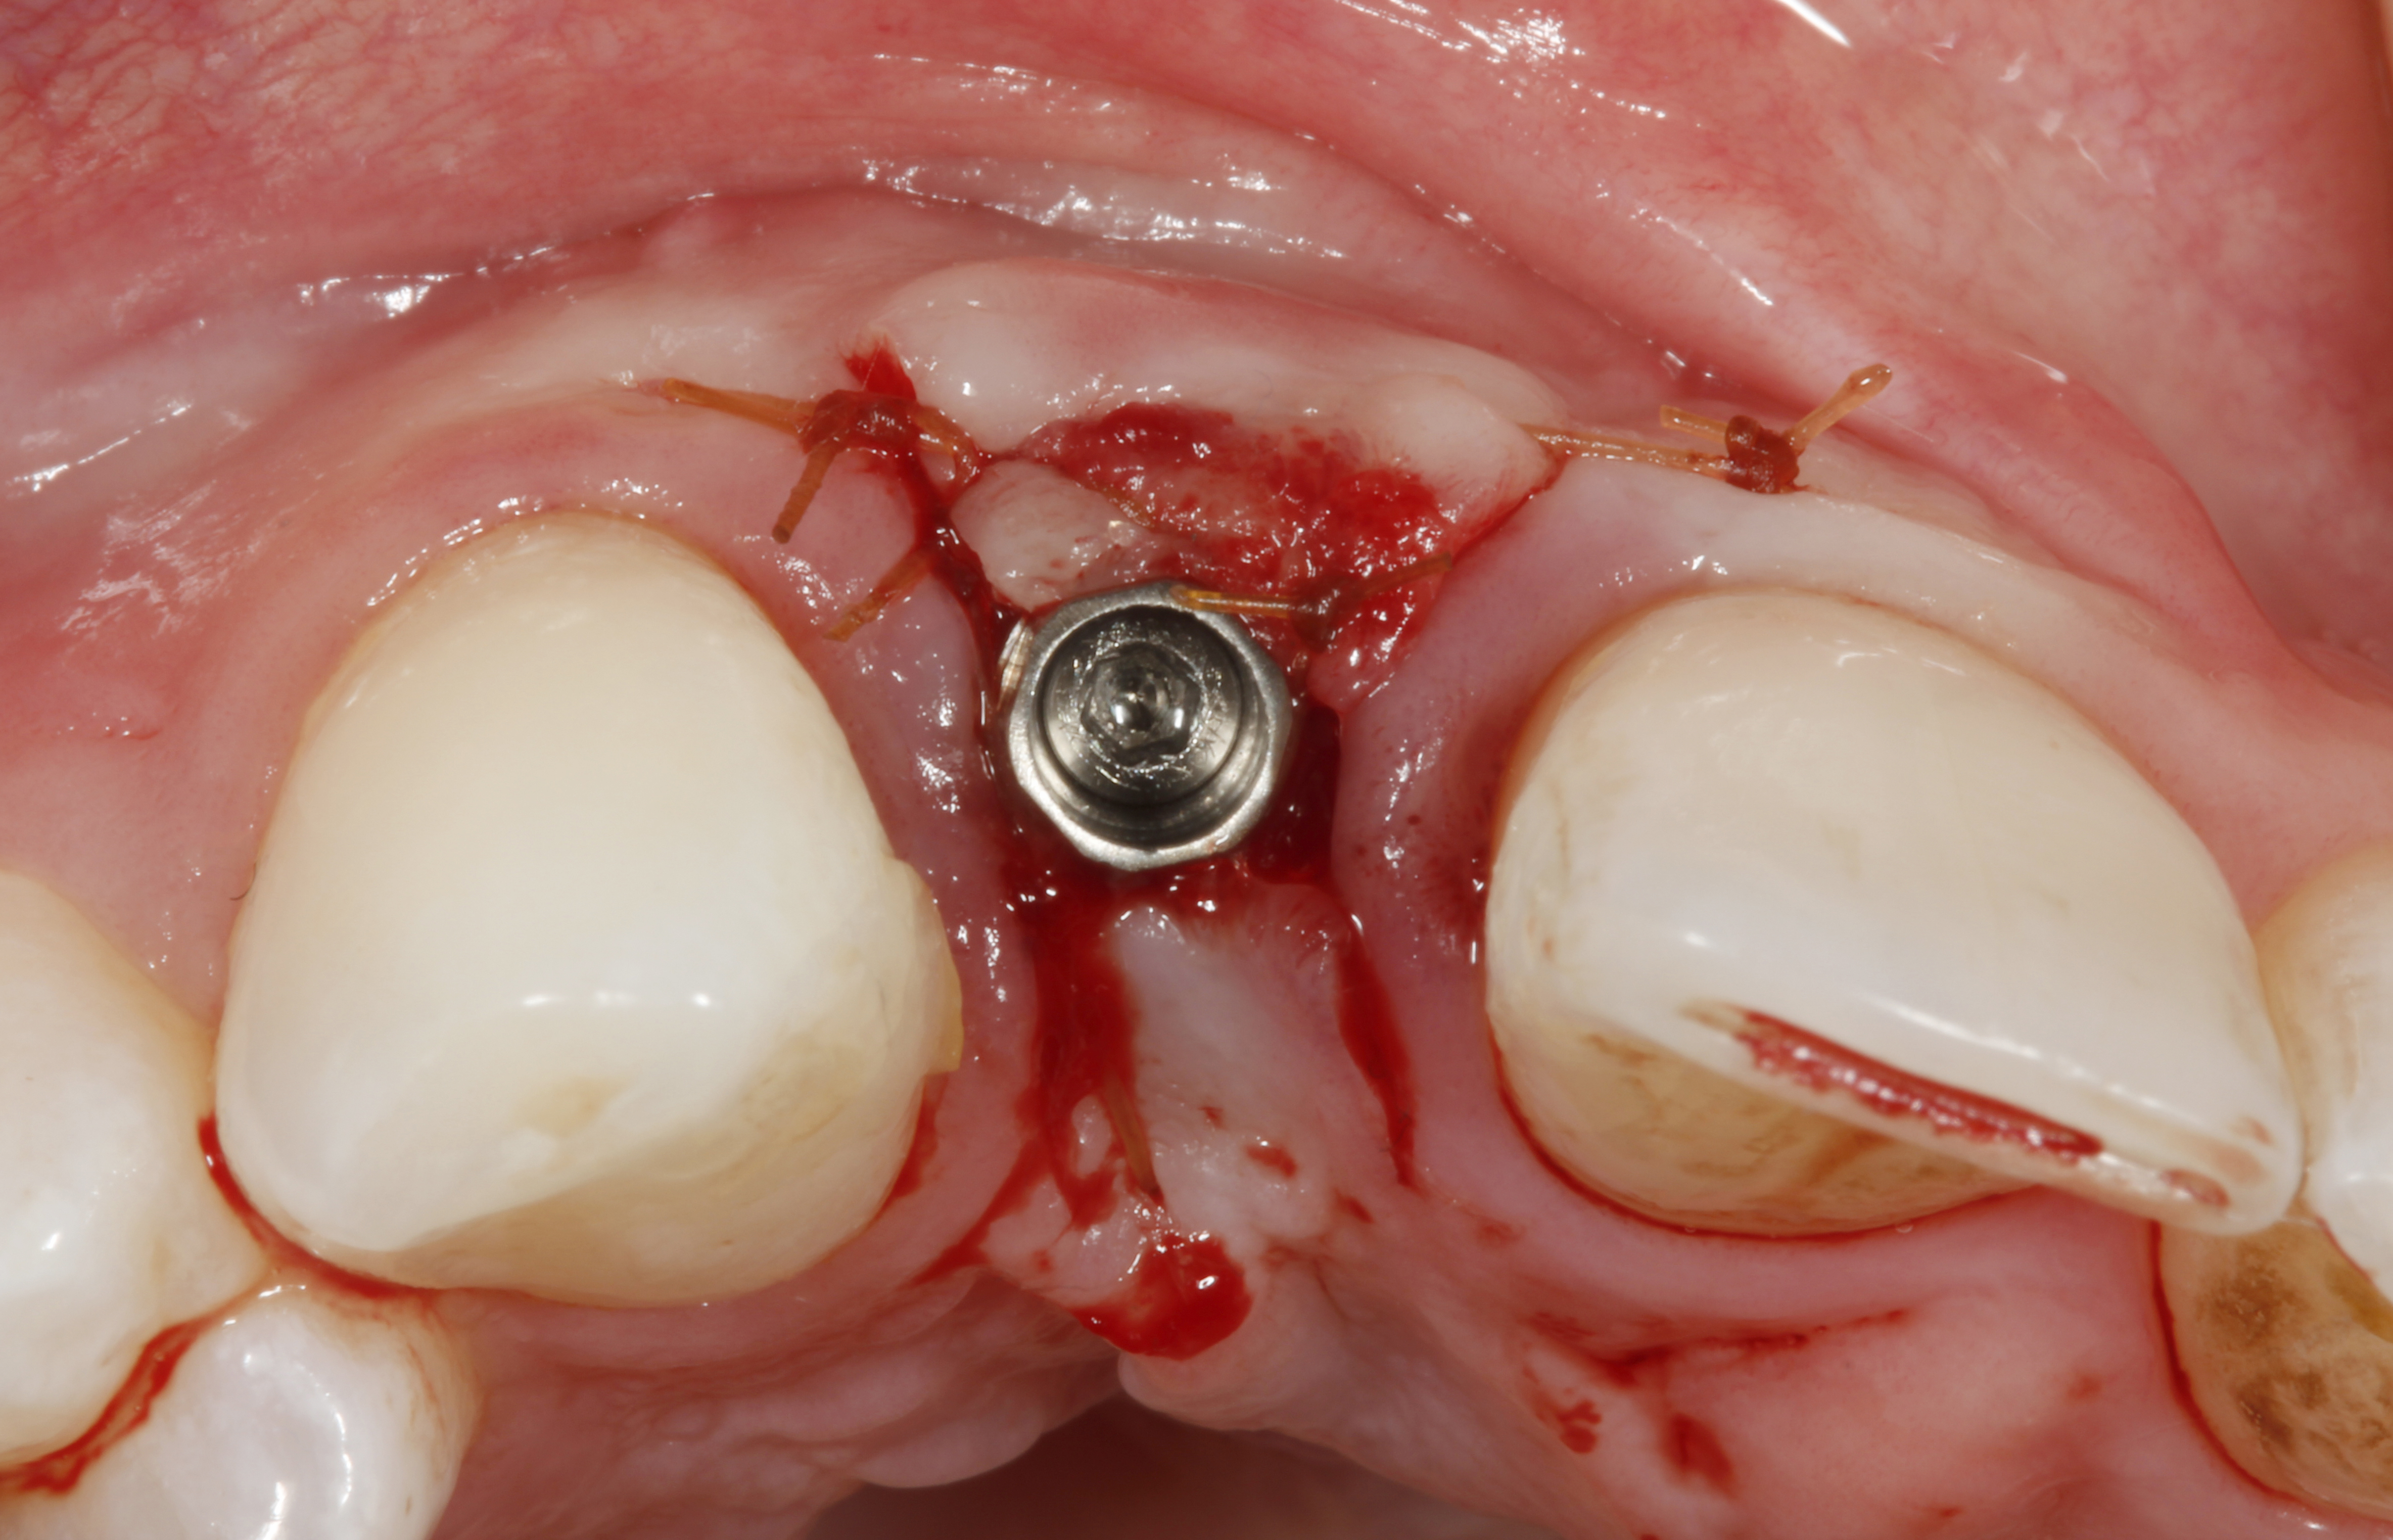

The crown and screw-retained custom abutment were removed, and a surgical cover screw was placed into the implant, thereby allowing spontaneous gingival augmentation in situ (Figure 33 and Figure 34). Note that the lingual aspect of the implant site was significantly more coronal than the labial aspect, which was positive because the defect would be limited to a facial–lingual defect. A fixed RBR bridge was cemented on the adjacent teeth and used as a tooth-supported transitional provisional restoration (Figure 35). A few weeks were allotted to let the soft tissue heal and migrate around the cover screw (Figure 36) to see if there would be complete coverage, thereby allowing a soft-tissue augmentation procedure to be performed with primary flap closure as in clinical scenario No. 2. The major obstacle in achieving a positive tissue response was that the implant depth was also deficient because the implant–abutment connection was at the level of the free gingival margin. It was decided that the best treatment option would be to remove the implant. A high-powered reverse-torque device (Fixture Remover Kit, NeoBiotech, www.neobiotechus.com) was used to remove the implant atraumatically (Figure 38 through Figure 41). The implant socket was allowed to heal for several months not unlike an extracted tooth (Figure 42). A new implant was placed in a better position from both a restorative and esthetic perspective (Figure 43), and after a few months of healing, a new crown was made (Figure 44). A satisfactory functional and esthetic result was achieved (Figure 45 and Figure 46) without employing pink porcelain.

Fig 33. Excessive facial angulation of the implant placement shown with an abutment driver in the access screw hole.

Fig 34. A surgical cover screw was placed in an attempt to decoronate the implant and gain soft-tissue coverage in situ.